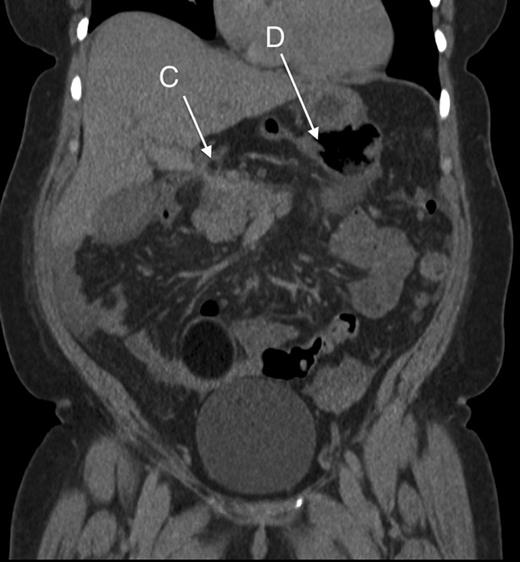

Computed tomography was used for diagnosis. Although initially reported as caecal volvulus, in hindsight there were features indicative of the herniation. (Figs 2 and 3).

Coronal section showing part of the colon passing behind the portal vessels (C) and a distended caecum in the lesser sac (D).